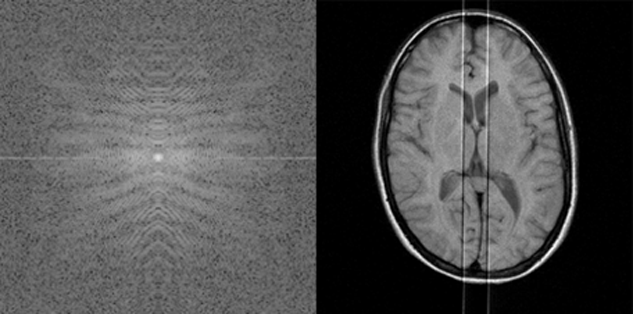

Figure 17-17:

k-Space artifacts: Aliasing or wrap-around artifact.

Figure 17-18:

k-Space artifacts: Radiofrequency feedthrough arti­fact.